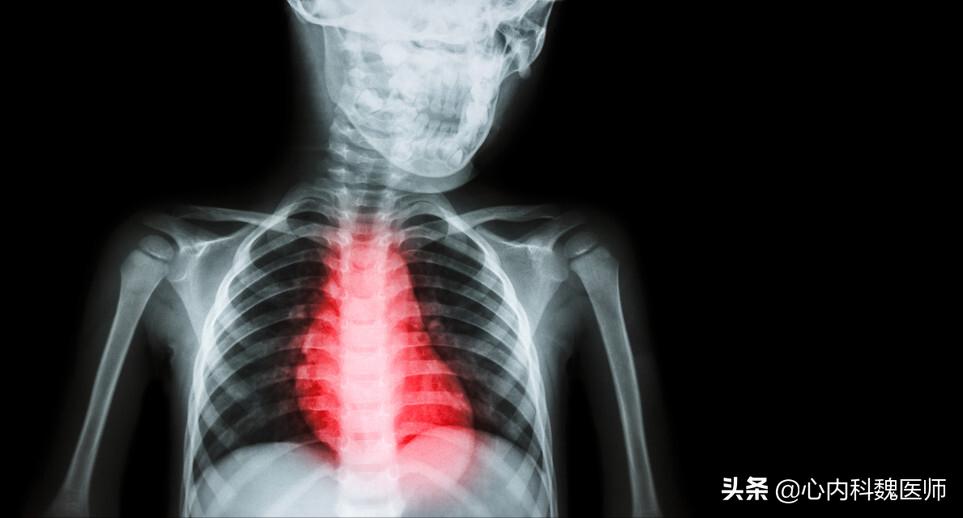

不得已,张阿姨再次到医院就诊,一番检查下来,心电图显示,窦性心律,存在室性期前收缩。胸片显示心影明显增大。心脏彩超更直观反映问题:张阿姨左侧心房、心室偏大,左心室后壁变薄,左心室舒张功能减退,二尖瓣重度反流,考虑为扩张型心肌病。

同时医生提醒张阿姨和她的家人,患者心脏存在明显扩大,Holter提示频发室性期前收缩,短阵室速,有发生恶性心律失常、猝死的风险,建议三腔起搏器置入(CRT-D),进行 心脏再同步化治疗 。